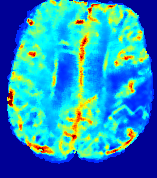

4.3.2 Diffusion Imaging via Advection-Diffusion

Slice #1Slice #2Slice #3Slice #4Slice #5Slice #6Dgtsuperscript𝐷gtD^{\text{gt}}Refer to captionRefer to captionRefer to captionRefer to captionRefer to captionRefer to captionDestsuperscript𝐷estD^{\text{est}}Refer to captionRefer to captionRefer to captionRefer to captionRefer to captionRefer to captionRefer to caption0.300.300.300.240.240.240.180.180.180.120.120.120.060.060.060.000.000.00(mm2/s)𝑚superscript𝑚2𝑠(mm^{2}/s)𝐕est𝟐subscriptnormsuperscript𝐕est2\|\bf{V}^{\text{est}}\|_{2}Refer to captionRefer to captionRefer to captionRefer to captionRefer to captionRefer to captionRefer to caption0.00300.00300.00300.00240.00240.00240.00180.00180.00180.00120.00120.00120.00060.00060.00060.00000.00000.0000(mm/s)𝑚𝑚𝑠(mm/s)

Figure 15: PIANO identifiability testing: diffusion imaging via advection-diffusion. Top row shows Dgtsuperscript𝐷gtD^{\text{gt}} used for simulating ground truth pure diffusion. Rows below show the estimated Destsuperscript𝐷estD^{\text{est}} and 𝐕est2subscriptnormsuperscript𝐕est2\|{\bf{V}}^{\text{est}}\|_{2} on corresponding slices. Note that the plotted value scale for 𝐕est2subscriptnormsuperscript𝐕est2\|{\bf{V}}^{\text{est}}\|_{2} is 0.01 of that for Dgtsuperscript𝐷gtD^{\text{gt}} and Destsuperscript𝐷estD^{\text{est}}.

Similarly, we test the behavior of PIANO when estimating both advection and diffusion from a pure diffusion-driven process. The goal is to determine if PIANO is able to recognize that there is only diffusion governing the given concentration time-series. We use the same ‘Diffusion Imaging’ data simulation of Sec. 4.2.1 as the concentration dataset, PIANO estimates both velocity 𝐕estsuperscript𝐕est{\bf{V}}^{\text{est}} and diffusivity Destsuperscript𝐷estD^{\text{est}}. Estimation results in Fig. 15 confirm PIANO’s identifiability again: the estimated 𝐕est2subscriptnormsuperscript𝐕est2\|{\bf{V}}^{\text{est}}\|_{2} is almost invisible compared to Destsuperscript𝐷estD^{\text{est}}, even plotted with a 1%percent11\% value range compared to that for Destsuperscript𝐷estD^{\text{est}}. On the other hand, Destsuperscript𝐷estD^{\text{est}} achieves comparable estimation performance as ‘Diffusion Imaging via Diffusion’ in which PIANO predicts Destsuperscript𝐷estD^{\text{est}} alone (shown in Fig. 13).